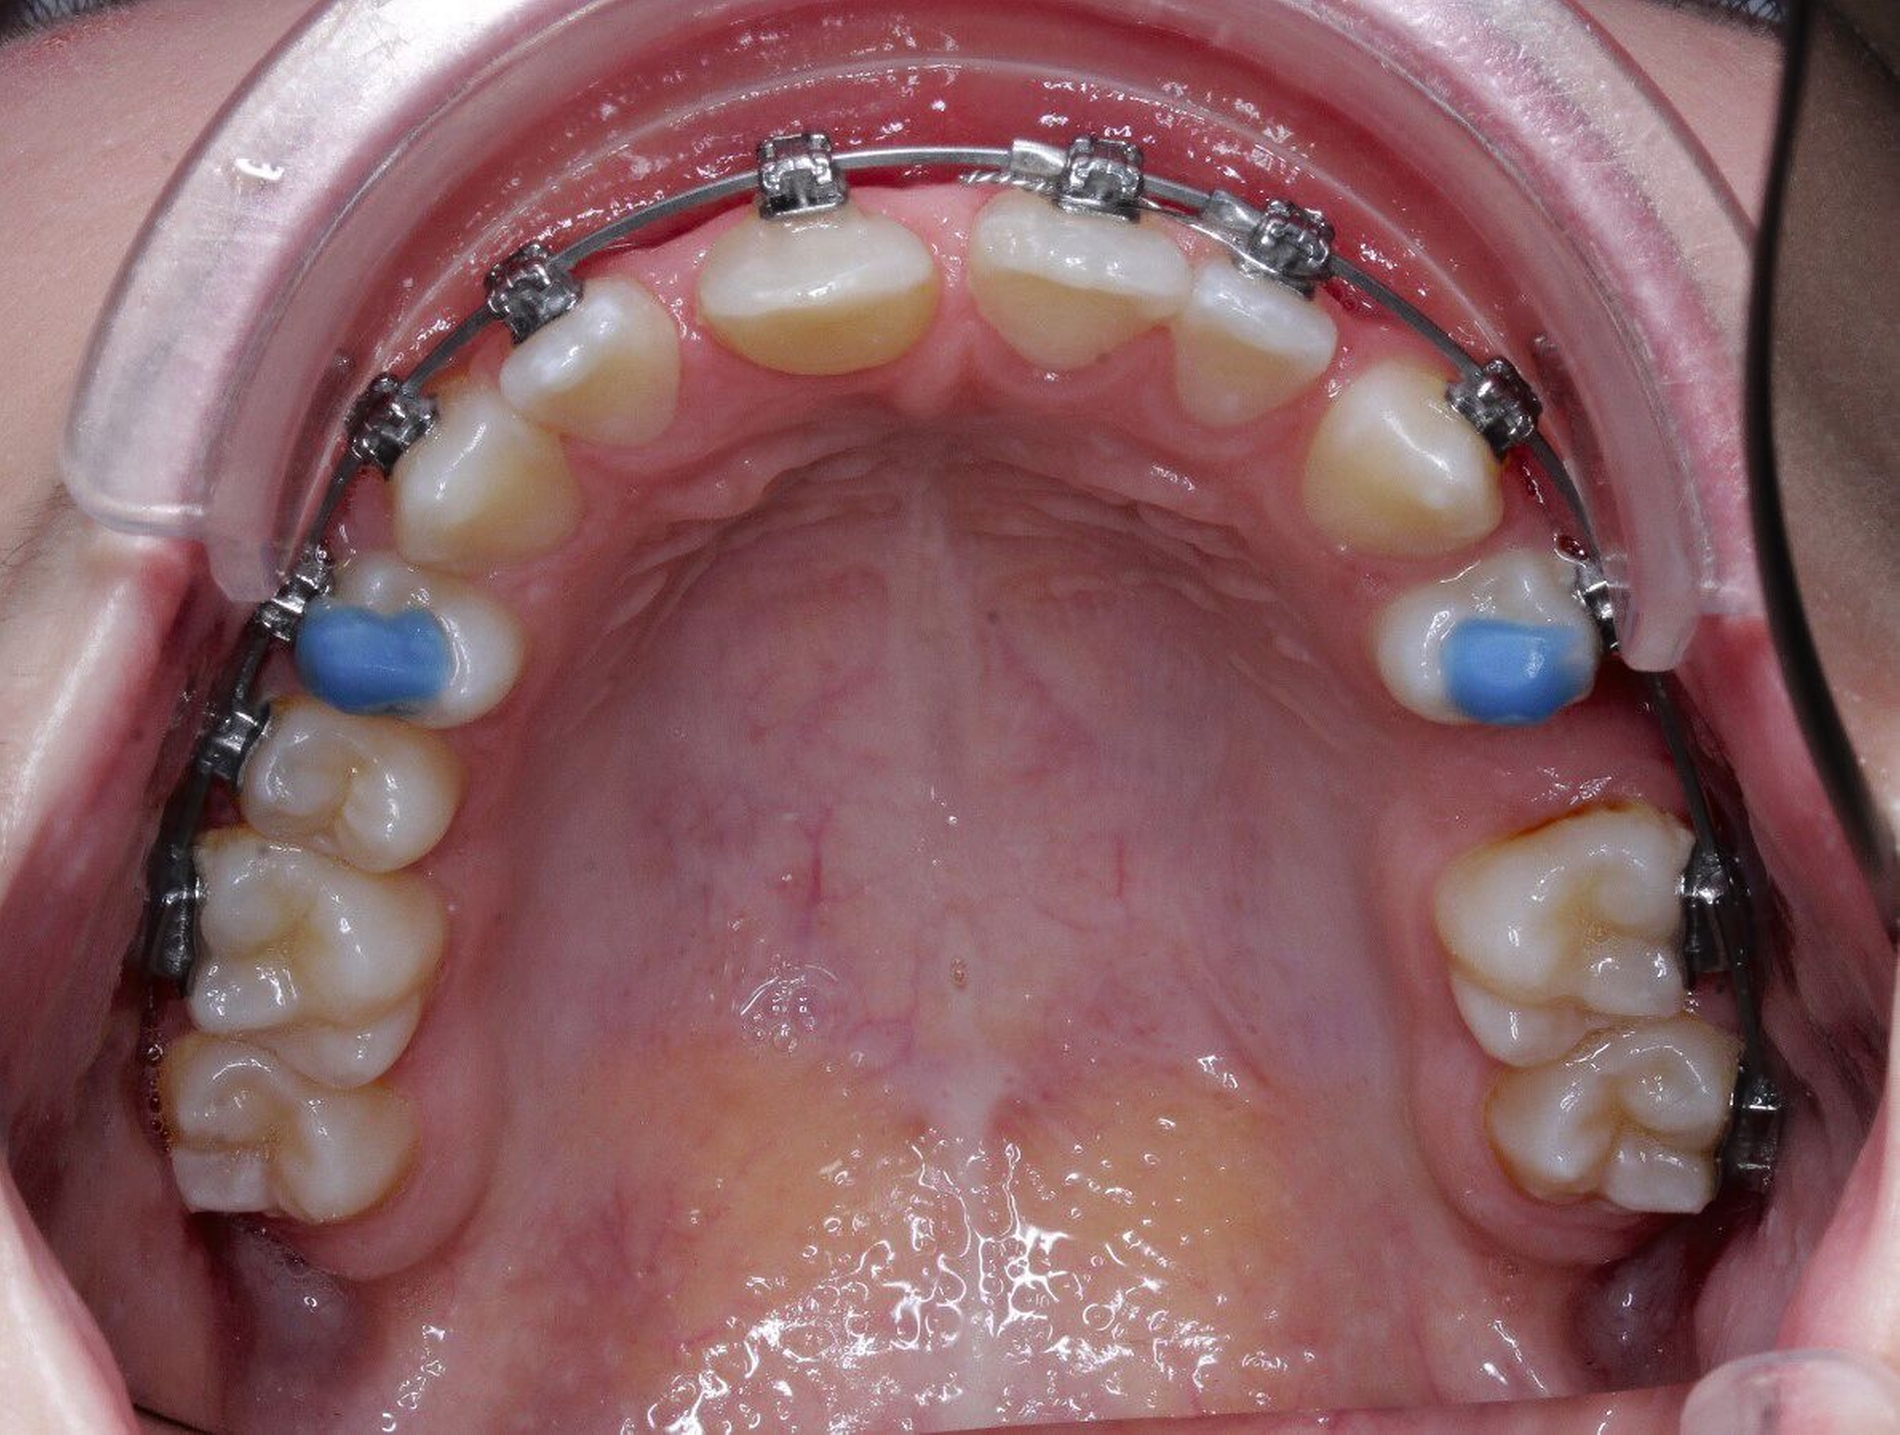

Im Alter von 13,2 Jahren – 4,2 Jahre nach der Milchzahn-TX – stellte sich die Patientin erneut in unserer Praxisklinik vor, um über die weiteren Therapiealternativen zu entscheiden. In enger Absprache mit der behandelnden Kieferorthopädin und den Eltern wurde die Prämolaren-Transplantation als weitere Therapie festgelegt. Auf Wunsch der Kieferorthopädin wurde aus gnathologischen Gründen der Zahn 25 als Transplantat gewählt.

Um störende okklusale Kontakte zu vermeiden, wurde der Zahn in eine leichte Infraposition gestellt und der Biss in der initialen Einheilphase von ein bis zwei Wochen leicht gesperrt, so dass die anschließende kieferorthopädische Extrusion des Zahnes ungestört durchgeführt werden konnte. Mit der kieferorthopädischen Bewegung und Feineinstellung des Transplantats wurde ab der vierten postoperativen Woche begonnen.

Durch die 90-Grad-Rotation des Transplantats stellt sich der Zahn anatomisch in der okklusalen Ansicht (Abbildung 7a) in der Sagittalen nahezu so breit dar wie der Nachbarzahn 21. Der adhäsive Frontzahnaufbau erfolgte drei Monate postoperativ noch unter der kieferorthopädischen Bracketierung. Die Weichgewebshöhe am Transplantat 11 ist durch die kieferorthopädische Extrusion ebenfalls als isogingival zum Nachbarzahn 21 zu erkennen. Der Klopfschall am TX-Zahn 11 war normoton und wies keine Ankylose auf. Die Sensibilitätsprüfung des Zahnes war positiv. Die Obliteration der Zahnwurzel weist auf eine vitale Reaktion des Pulpagewebes hin, wie man sie auch bei erfolgreich replantierten jugendlichen Zähnen beobachtet.